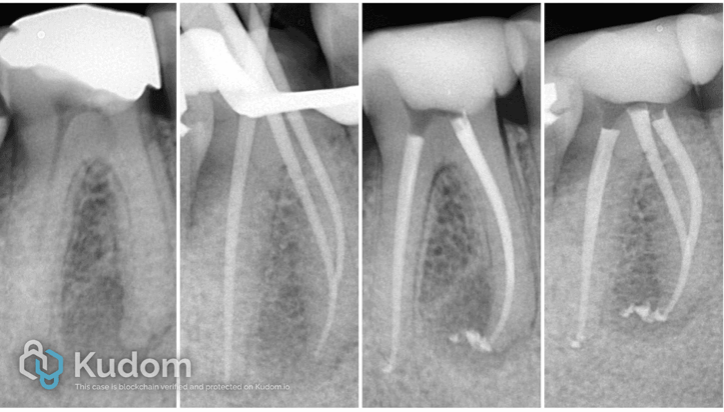

Fig. 2

The pre-operative radiograph show two adjacent lower molars restored with large amalgam restorations. Both restorations show signs of failure, particularly at the proximal area between the two teeth. In the first molar, there is loss of normal pulpal architecture with a periapical radiolucency, indicative of pulp necrosis and associated periapical pathology. The second molar appear radiographicaly normal with no periapical changes , and it’s gives possitive response to the vitality testes .

These clinical and radiographic findings support the need for endodontic treatment for the necrotic tooth, followed by appropriate definitive restorative management for both molars.

Fig. 3

After removing old amalgam restoration , recurrent caries from the lower six , the tooth was isolated using a rubber dam, the canals orifices were located, the root canals were enlarged, shaped cleanend , and then Obturated with a single cone with bioceramic sealer

Fig. 4

Periapical radiographs Illustrated the endodontic treatment of lower 6 adequate shaping , cleaning, and three-dimensional obturation of the root canal system, suggesting a favorable prognosis.